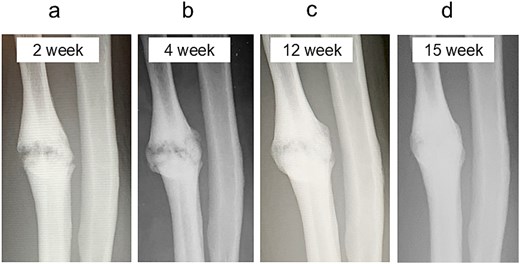

A 54-year-old man sustained a mid-diaphyseal ulnar fracture from a direct kick during karate practice. Initial conservative treatment at another hospital failed to achieve union over 12 months, and he was referred to our clinic with a diagnosis of nonunion. At presentation, he reported significant pain with a numerical rating scale (NRS) score of 6, and radiographs showed a 9 mm interfragmentary gap (Fig. 1a and b). Given his pain, we initiated proactive conservative management with prolotherapy, primarily targeting pain relief. Ultrasound revealed marked doppler signals at the nonunion site, suggesting inflammation and neovascularization. A mixture of 6 ml 50% dextrose and 4 ml 1% lidocaine (final 30% dextrose) was injected under ultrasound guidance into the neovascularized tissue and fracture gap (Fig. 2a and b). From the second session onward, bone healing had progressed to the point where the solution could no longer be injected between the bone fragments, so subsequent injections were administered around the periosteum. No restrictions were placed on weight-bearing or activity. Pain improved to NRS 4 at 2 weeks and to NRS 2 at 4 weeks, with early callus formation seen on radiographs. Prolotherapy was repeated five times at 2–3 week intervals. By 12 weeks, the patient was pain-free (NRS 0) and returned to karate. Radiographic union was confirmed at 15 weeks (Fig. 3a–d). Although initiated for pain control, prolotherapy led to relatively early bone union without surgery or complications.

Radiographic findings during follow-up. (a) At 2 weeks, early callus formation is observed. (b) At 4 weeks, increased callus formation is noted. (c) At 12 weeks, near complete union is evident. (d) At 15 weeks, complete union achieved.